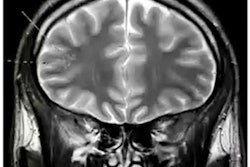

Advanced visualization and artificial intelligence (AI) software developer Coreline Soft is directing attention to recent research involving its coronary artery calcium (CAC) image analysis software.

In a population study involving 997 participants from the Robinsca CAC screening clinical trial in Europe, the company's AI-based Aview CAC software yielded 99.2% accuracy for categorizing risk compared with an experienced reader's interpretation of the low-dose CT exams, according to the researchers from the Institute for Diagnostic Accuracy (iDNA) at the University Medical Center Groningen in the Netherlands.

"The deep learning-based software for automatic CAC scoring can be used in a cardiovascular CT screening setting with high accuracy for cardiovascular risk categorization and initiation of preventive treatment," said senior author Dr. Matthijs Oudkerk, PhD, in a statement from Coreline.